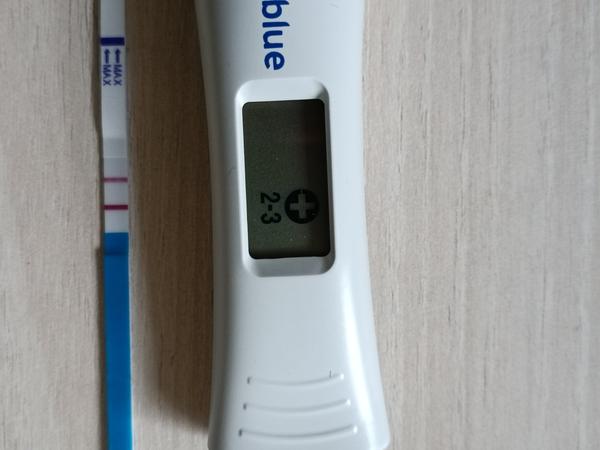

- Těhotenský proužkový test může být pozitivní už 7. den po embryotransferu, ale intenzita čárky se liší podle značky testu a nelze ji mezi různými testy přímo porovnávat.

A: Proužkový test může být pozitivní již 7 dní po ET, ale intenzita čárky závisí na značce; spolehlivější je odběr krve pro stanovení hCG, v diskuzi byla ve 15. dni po ET uvedena hladina 7428 IU/l.

- Těhotenský proužkový test může ukázat pozitivní čárku velmi brzy po ET, ale intenzita čárky není spolehlivý ukazatel vývoje.

- Někteří považují intenzitu testovací čárky za indikátor vývoje (očekávají zesílení každý druhý den), zatímco jiní zdůrazňují, že různé značky testů a barviva tento údaj zkreslují.

Je to dnes cca 7 den a čárka je pěkná. Už to není duch, je to krásně viditelné. Přeji, ať to dopadne. Také jsme tím v rodině procházeli několikrát, jsou to hrozné nervy,

Vím, že být v klidu nejde. Obden by čárka měla být jednou tak silná. Pak je vidět, že se těhotenství vyvíjí tak, jak má.

@renatajaja To je krásná čárka na 7DPT. Já byla na KET 8.9. a 7 den jsem ji teda tak pěknou neměla... ❤

@renatajaja nemůžeš porovnávat 2 různé testy, každá značka má jiné množství barviva. Je krásně pozitivní, hodně štěstí 🍀🍀🍀

@renatajaja Test vypadá krásně... když na to koukám, tak ty čárky máme podobný... taky jsem si říkala, jestli by neměly být silnější. Já jdu na krev zítra. Tak nám moc držím palce. ❤

@lenie82 ahojky, já udělala test ještě naposledy dnes . Držím nám oběma a miminkám pěstičky, aby vše dobře dopadlo ❤️🙏

@renatajaja no to je krasny! To vypada moc dobre!